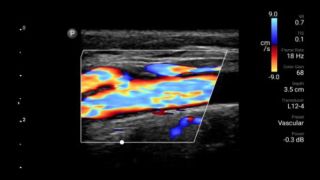

Start treatment with an accurate diagnosis

Lumify helps you see the fine details in muscles, joints, ligaments, tendons and cartilage to make a more accurate diagnosis of injuries.

Respond fast with whole-body imagery

Lumify can help you assess patients from head to toe, whether it’s plantar fasciitis, tendonitis or bursitis in the patellar tendon, or even shoulder instability in the rotator cuff.

Get the clarity of larger ultrasound systems with Lumify

SonoCT reinforces real tissue imaging while eliminating random artifacts. This technology produces images superior to conventional imaging in up to 94% of patients.

Lumify transducers for MSK

Lumify L12-4 broadband linear array transducer